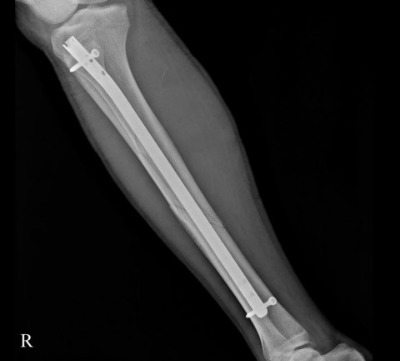

2.jpg 정강이 골절 (출처 : 본인)

그에 반해 나는 되돌릴 수 없는 실패를 두 번 겪었다. 중상을 입어 필드에서 치워졌던 경험이다. 10년 전엔 우측 정강이가 골절되었고, 2년 전엔 목디스크 판정을 받았다. 사실 정강이 골절부터 내겐 무리한 부상이었지만 이를 받아들이지 않았다. 재활에 상당한 노력이 들지만 재기에만 성공한다면 실패를 만회할 수 있으리라는 생각 때문이었다. 과거의 나를 치유해주고 싶은 마음과 고집이라고 봐야겠지.